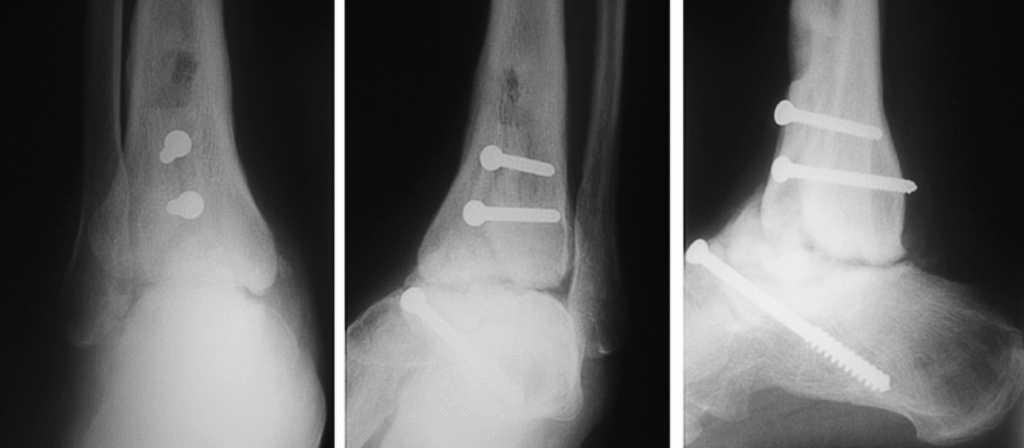

El seguimiento a la largo plazo de las fracturas del astrágalo identifica que la causa más común de los resultados pobres está asociada con la OA subastragalina, tibioastragalina y talonavicular, tanto en nuestra revisión, que alcanzó al 21% (8) de los casos (figs. 9 y 10), como en otros trabajos revisados15,17,19,22,23.

Fig. 9. --A) Fractura del cuerpo del astrágalo tipo B más rotura completa de los 3 ligamentos laterales del tobillo. B) Abordaje bilateral. Osteosíntesis. Sutura de ligamentos. Radiografía y tomografía computarizada a los 18 meses. Artrosis subastragalina y tibioastragalina.

Fig. 9. --a: Type B fracture of the astragalus with complete rupture of the 3 lateral ankle ligaments. b: Bilateral approach. Osteosynthesis. Ligament suture. Radiography and CT at 18 months. Sub-astragalar and tibio-astragalar arthrosis.

Fig.10. --Resultado a los 32 meses. 50° de BA. NAV del cuerpo y artrosis subastragalina y tibioastragalina

Fig.10. --Results at 32 months. BA 50º. Avascular necrosis of the astragalus and sub-astragalar and tibio-astragalar arthrosis.